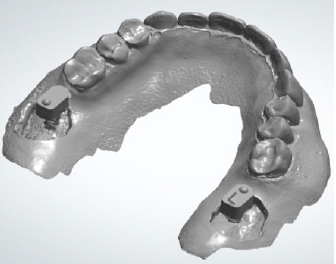

At the end of the surgical session, the position of the implants was defined by the use of specific scan bodies connected to each other through the use of the universal scan template. Then, the post-surgical digital scan was carried out, including the entire maxilla, the skeletal scan bodies, the implant scan bodies and the universal scan template (Figure 14).

Figure 14: Post-surgical digital scan including the entire maxilla, the skeletal scan bodies, the implant scan bodies and the universal scan template.

As seen in the previous case, in the resulting post-surgical intermaxillary space, a fixed full-arch temporary prosthesis was digitally designed and manufactured in a complete digital workflow (CAD/CAM) with the occlusal plane parallel to the Camper’s plane and the bipupillary plane, it was then screwed on the implants (Figures 15-22). The definitive prosthesis will be fabricated once the implants are integrated and both hard and soft tissue are healed and stable.

Figure 15: Maxillo-mandibular relationship in patient’s habitual occlusion in maximum intercuspation obtained matching the pre-surgical and post-surgical digital scans.